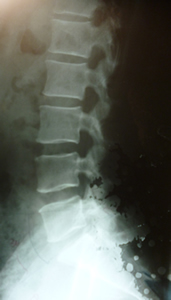

平背と腰痛症

腰椎は正常に保たれています腰仙角の角度が大きくなっています 原因の指導と

理解で自然的弯曲を取り返しました。